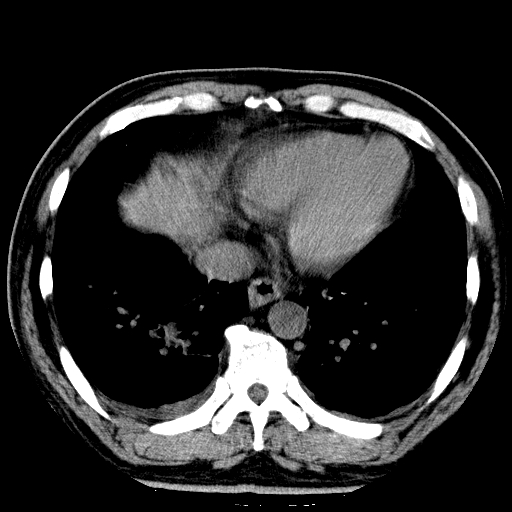

男,65岁,咳嗽、咳痰、发热5天。

支持慢性支气管炎伴感染,双侧少量胸腔积液.

两肺间质纤维化,支扩合并感染,双侧胸腔积液

慢性支气管炎并感染,支扩,双侧少量胸腔积液.